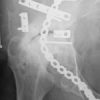

Una fractura de cadera es una quebradura en la parte superior del hueso del muslo (fémur) donde el hueso del muslo se une a la pelvis para formar la articulación de la cadera.

La mayoría de las fracturas de cadera ocurren en la zona que se encuentra justo por debajo de la bola del fémur (región del cuello femoral) y en la zona que se encuentra justo por debajo de esta (región intertrocantérea). Una fractura de cadera casi siempre quiebra el hueso por completo. Podría ocurrir una quebradura parcial en el hueso (fractura fina).